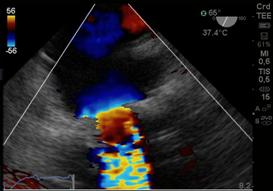

Analizamos la vena contracta (el orificio fisiológico de la regurgitación, es el cuello o la parte más estrecha del jet distal al orificio regurgitante), IM leve < a 3mm y severa mayor a 7mm. Luego el orificio regurgitante efectivo y el volumen regurgitante por los métodos de convergencia del flujo o área de la superficie de isovelocidad proximal (PISA) y de cuantificación(21) PISA(22) se basa en un principio hidráulico, donde la sangre que se aproxima a un orificio circular va formando capas concéntricas de isovelocidad creciente y superficie decreciente. En condiciones ideales, en un orificio circular pequeño sobre una superficie plana, estos contornos de isovelocidades tienen una forma hemiesférica. Por el principio de continuidad, el flujo en cada uno de estos contornos es igual, y a su vez igual al flujo a través del orificio valvular. Si podemos calcular el área de cualquiera de estos contornos y estimar su velocidad podemos calcular el flujo (flujo=Area x velocidad) (Figura16). Si la forma de los contornos de isovelocidad es hemiesférica entonces:

La velocidad de la hemiesfera, la obtenemos del mapa color donde ocurre el primer aliasing.

Ajustamos la velocidad de aliasing, para poder ver la hemiesfera circular y asumiendo que el máximo radio de esa hemiesfera coincide con la máxima velocidad de la IM, se puede calcular el orificio regurgitante efectivo con la siguiente fórmula:

Donde Va es la velocidad de aliasing y la Vreg pico, es la velocidad pico de la IM tomada con Doppler continuo. Y cuando ORE es mayor de 0.4 cm2 es IM severa y ORE menor de 0.2 cm2 es leve.